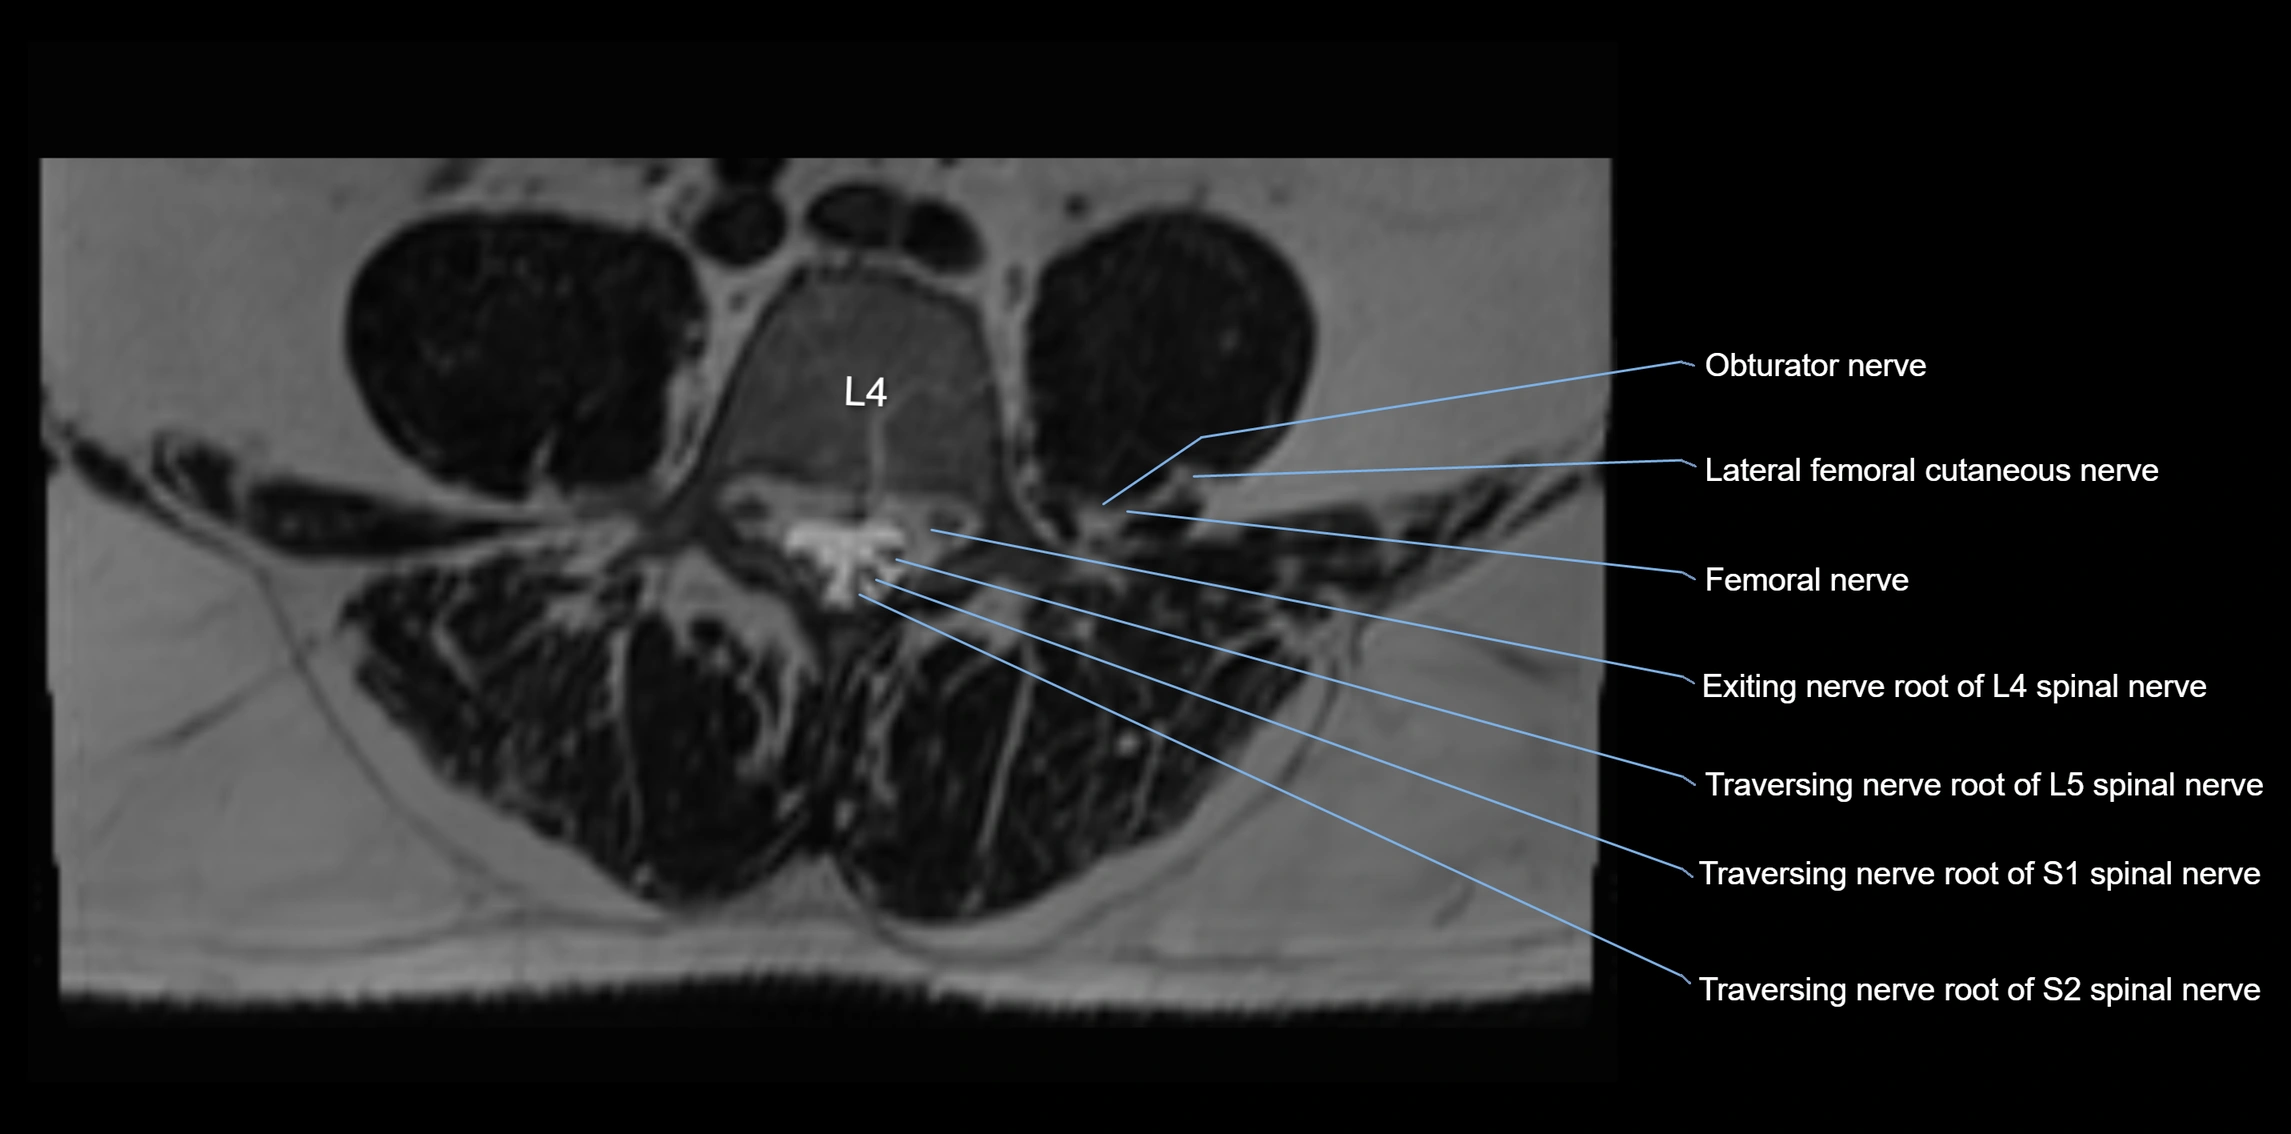

MRI Appearance

T1-weighted images:

• Nerve appears as a very thin low-to-intermediate signal intensity structure

• Surrounded by bright fat, aiding visualization

T2-weighted images:

• Nerve shows intermediate to mildly hyperintense signal compared to muscle

• Pathological involvement appears brighter

STIR (Short Tau Inversion Recovery):

• Normal nerve appears dark

• Inflamed or entrapped nerve appears bright hyperintense

T1 Fat-Sat Post-Contrast:

• Normal nerve enhances minimally

• Pathologic nerve (neuritis, entrapment, tumor infiltration) shows focal or diffuse enhancement

3D T2 SPACE / CISS:

• Nerve appears intermediate to mildly hyperintense compared to muscle

• Surrounded by bright fat or CSF, improving visualization

• Best sequence for mapping small pelvic nerves such as the anococcygeal